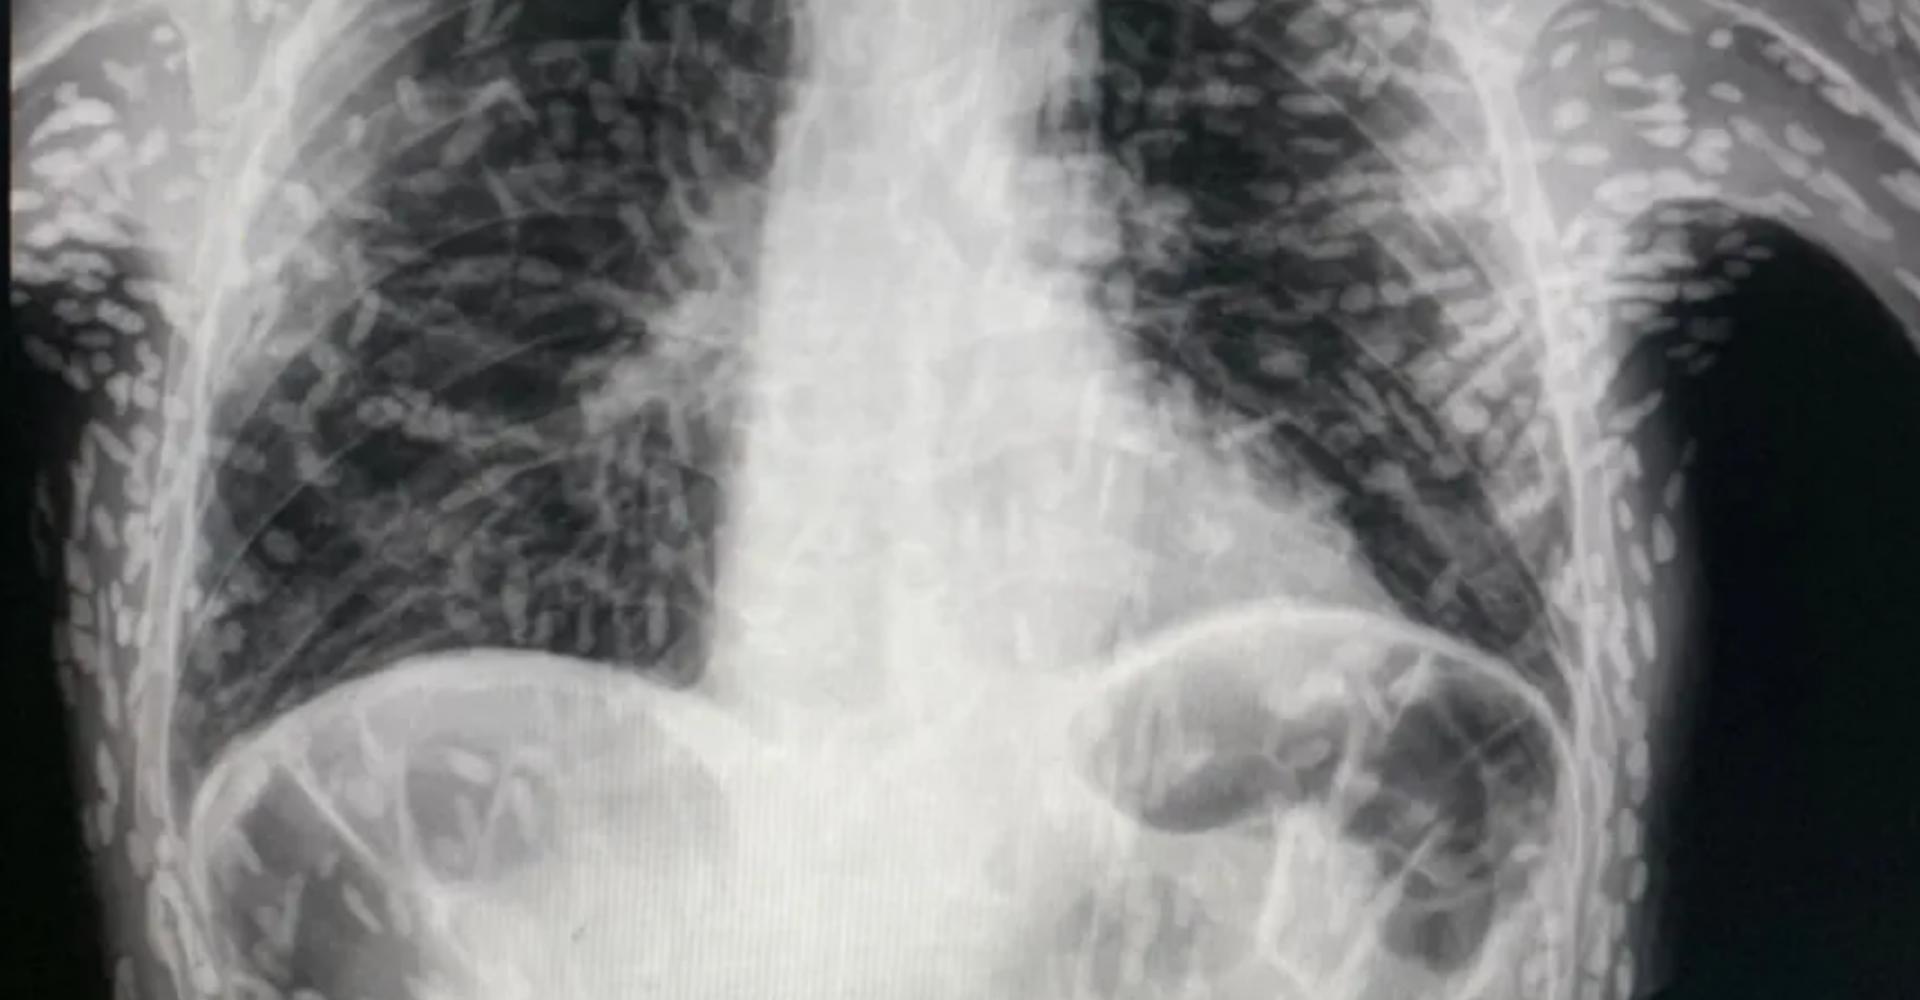

Um exame de radiografia de tórax, que circula nas redes sociais nos últimos dias, impressiona.

O raio-x foi publicado no Twitter pelo médico Vitor Borin de Souza, residente pelo Hospital das Clínicas da Faculdade de Medicina Botucatu (HCFMB), da Universidade Estadual Paulista (Unesp).

Segundo o médico, o exame é de um paciente que apresentava tosse há dois meses. O diagnóstico é de cisticercose disseminada.